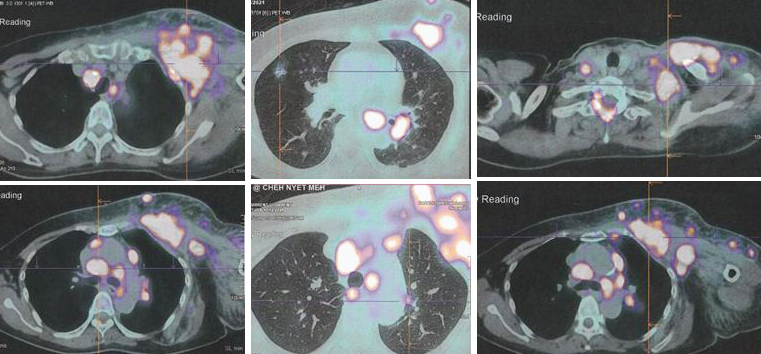

Due to the massive metastasis as shown in the PET scan done on 10 December 2021, Lucy had no choice but to proceed with chemotherapy. Indeed the cancer had spread extensively.

8. PET scan on 14 April 2022 showed good response indeed.

1. Amazing results of chemotherapy. Compare these three pictures –

Left: After surgery Lucy was on alternative therapy, refusing to undergo chemotherapy. The result was extensive metatastasis (middle). Right: Lucy has no choice but to go for chemotherapy. The outcome of 6 cycles of chemotherapy was just fantastic! In my 25 + years dealing with cancer patients, I have never seen such a great outcome of chemotherapy. Salute the oncologist! You rescued her!

In fact, the results were so unbelievable that one is tempted to ask if it is for real and not a fake? My answer is NO, detailed study of the PET scan results below are real! Study the images carefully – those before and after  chemotherapy.